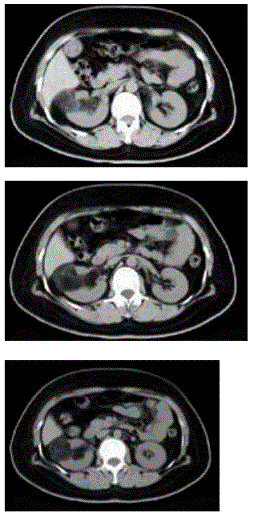

问题 男,55岁,因右腰部不适1年余,行CT扫描如图所示,下列说法正确的是( )

选项 A、考虑为右肾癌 B、考虑为右肾错构瘤 C、其内见低密度脂肪影 D、其边缘清楚,与周围境界清晰 E、右肾中极可见一类圆形肿块影,肿块密度不均

答案 BCDE